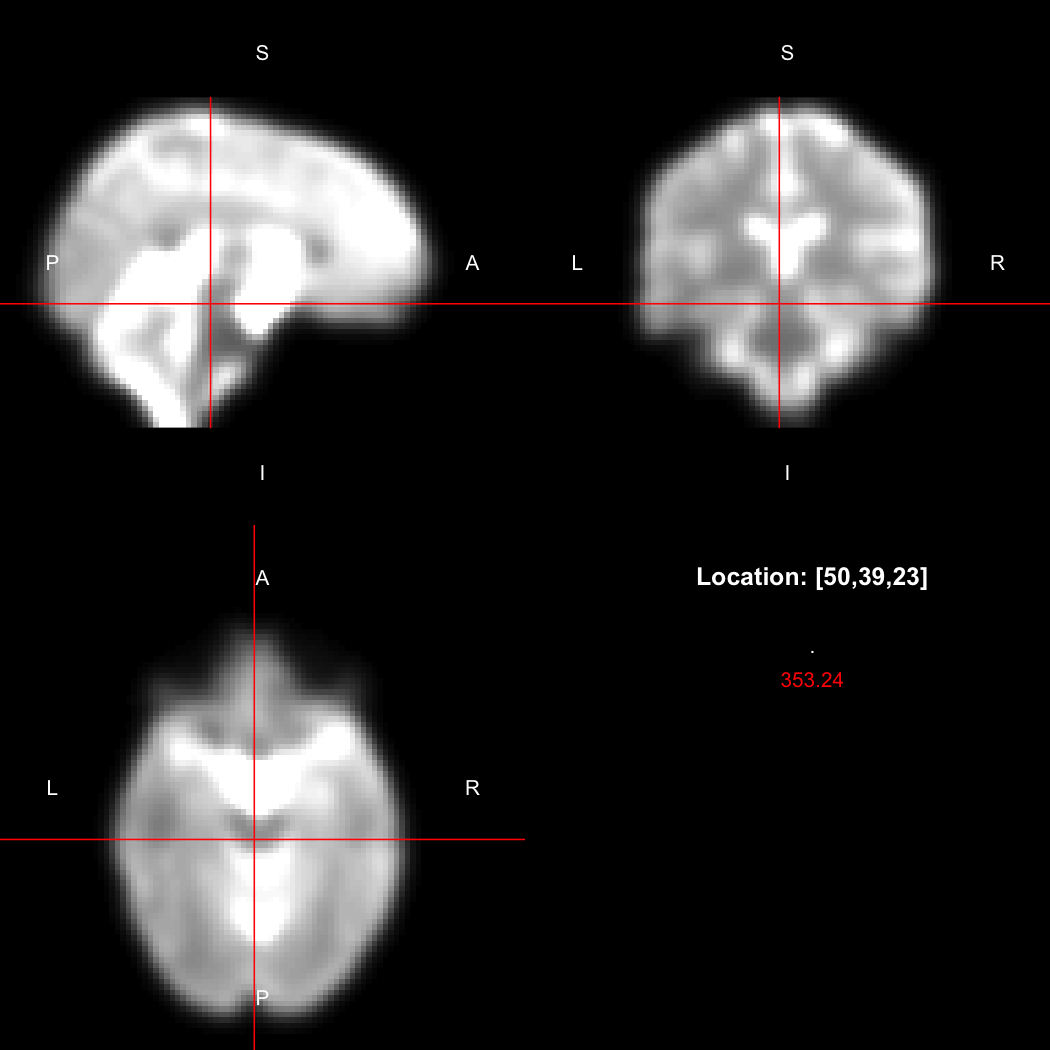

We can also use the RNifti image viewer to visualise the image.

view(image)

plot of chunk original